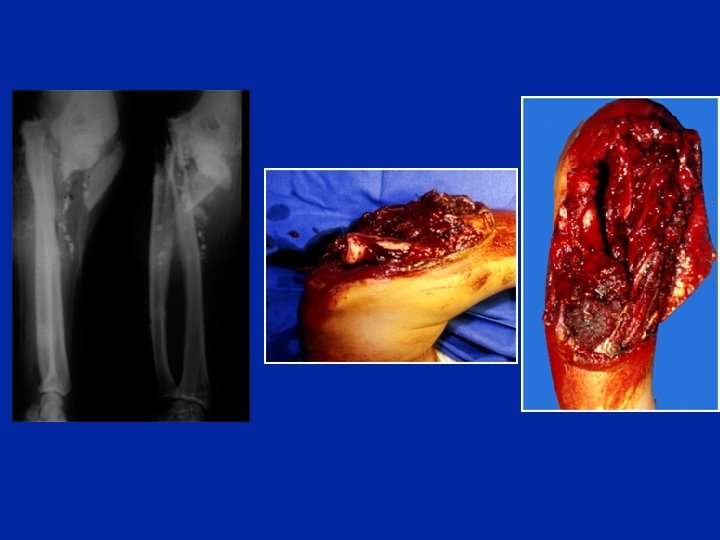

ANAPATH • B/Les lesions associées : • l’ouverture cutanée : rare, sauf dans les traumatismes directs ; aggravant le pronostic de la fracture. • le délabrement musculo-périosté. • les lésions vasculo-nerveuses : rare.

EXAMEN CLINIQUE TDD : Fr des 2 os de l’AB déplacée chez l’adulte. 1 -inspection : *attitude du traumatisé du membre supérieur *impotence fonctionnelle totale du membre supérieur *déformation de l’AB en crosse, en baïonnette, ou en ventre de fourchette. *œdème rapidement expansif de tout l’AB. 2 -palpation : -la mobilisation de l’avant bras déclenche une douleur. -recherche d’une complication vasculonerveuse : palpation des pouls, examen neurologique.

TRT chirurgical s’adresse à l’adulte et à quelque fr chez le grand enfant. -les plaques vissées indiquées chez l’adulte ; permettent une rééducation précoce. -l’embrochage : utilisé surtout chez l’enfant. -le fixateur externe : utilisé dans les Fr complexes et les délabrements musculaires.